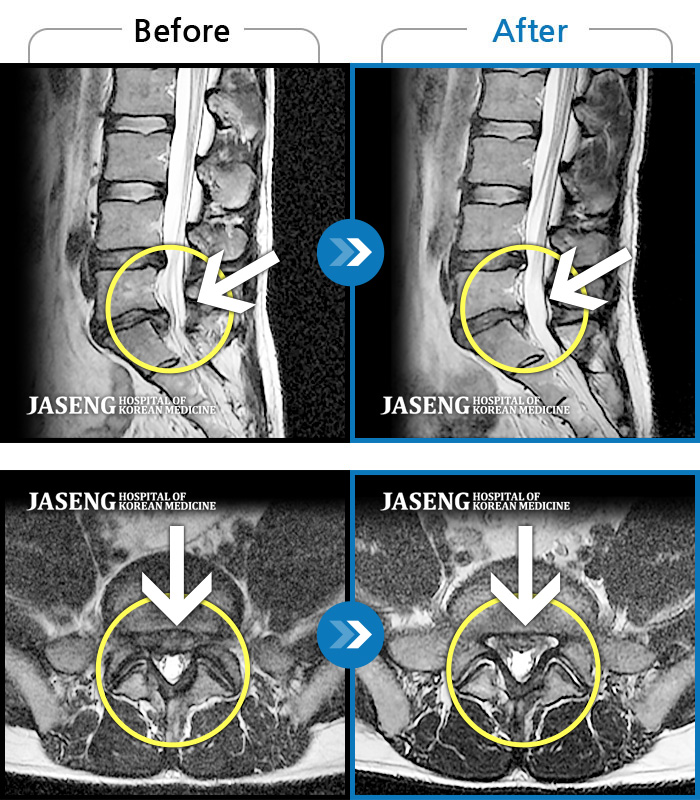

MRI 치료사례

허리통증으로 보행 불가 및 거동 불가, 좌측 둔부 통증